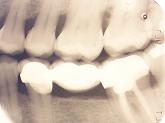

La forma de detectarlas es mediante inspección visual y radiológica(aletas de mordida especialmente).

Mediante éste último método es posible localizar caries ocultas y de un

tamaño reducido, antes de que puedan manifestar síntomas.